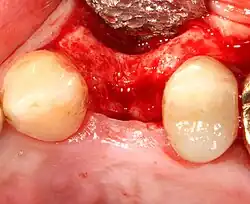

Реконструкция твёрдых тканей

Восстановление мягких тканей